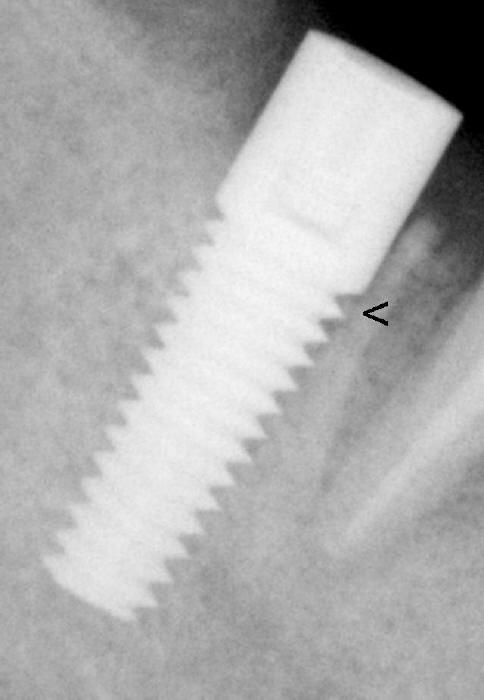

Fig.16: Four months post implantation.  Bone appears to have grown into the implant threads (<).